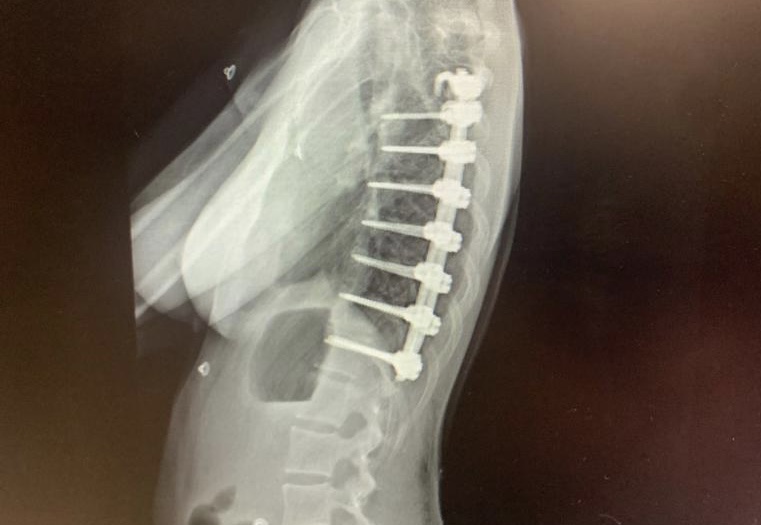

Mayagüez Orthopedics PSC., es el grupo médico ortopédico del Dr. Carlos Pérez Cardona, el Dr. Carlos J. Pérez López y el Dr José C. Pérez López. Nuestra meta es proveer servicios de calidad y excelencia a nuestros pacientes que padecen una variedad de problemas ortopédicos brindándoles una mejor calidad de vida. Nuestra práctica se especializa en ortopedia, medicina deportiva y columna, la cual conlleva la evaluación y el tratamiento de los huesos, coyunturas, músculos, tendones y nervios. Ambos cirujanos son board certified.